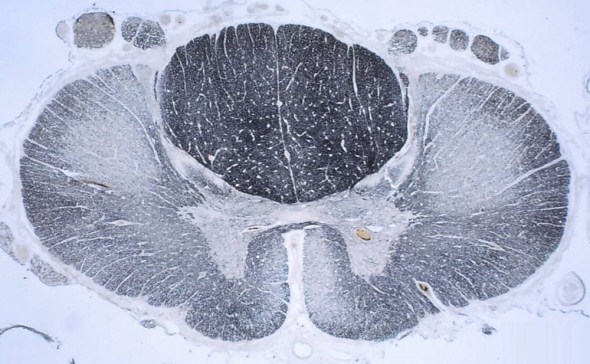

Know your spinal cord – The landmarks

A human cervical spinal cord slice. Once you’ve read this post, you should be able to identify the major parts and tell which side is the front of the cord.

Welcome to day thirty-three in our series. For those of you who are just finding us, we have every one of these posts in our neuroanatomy category in reverse chronological order. Today we’re going to backtract (get it?) a little and go over something basic, but something we’ve skipped over to this point. We never really talked about the landmarks of a spinal cord slice. So today, we are going to take a detour and go over spinal cord features.